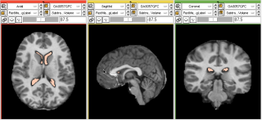

Panels and their use

File:Bver icon.png

User Interface